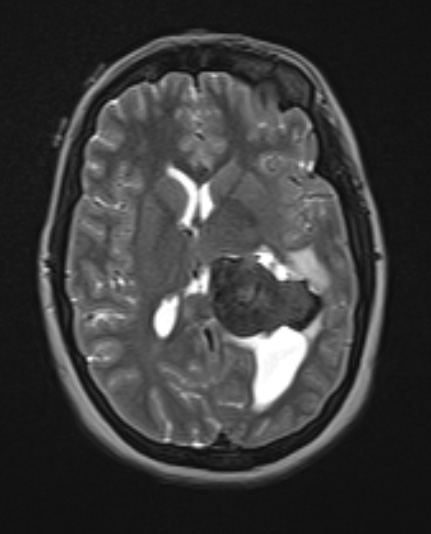

Washington University Experience | NEOPLASMS (MENINGIOMA) | Gross Pathology | 20A4 Meningioma, intraventricular T2W (Case 20) axial - Copy - Copy

This T2-weighted contrast administered image shows a variegated, largely hypointense image.